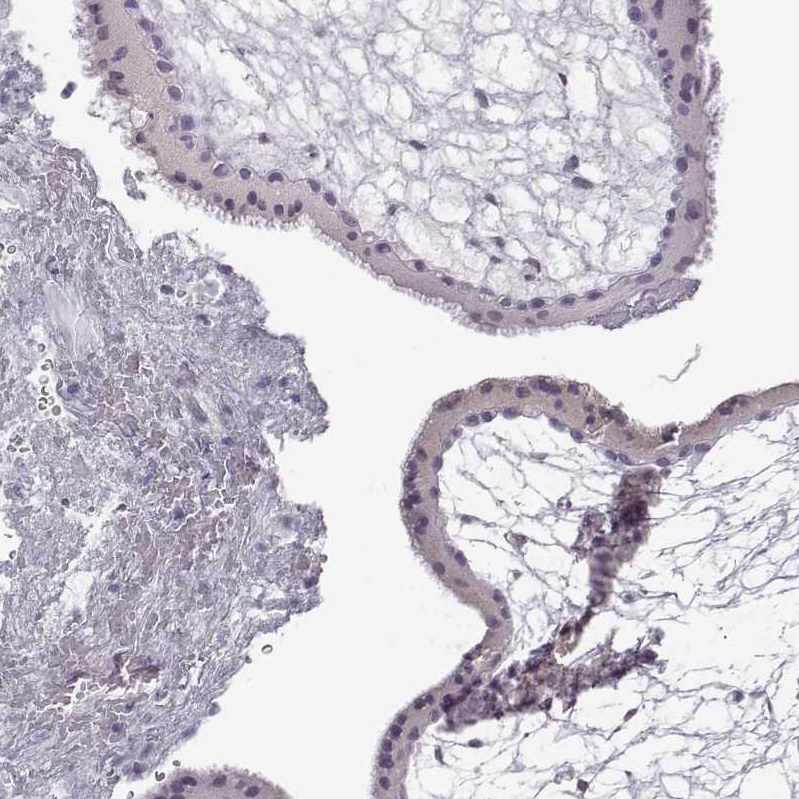

Immunohistochemistry analysis in human cerebral cortex and prostate tissues using HPA055177 antibody. Corresponding VGF RNA-seq data are presented for the same tissues.